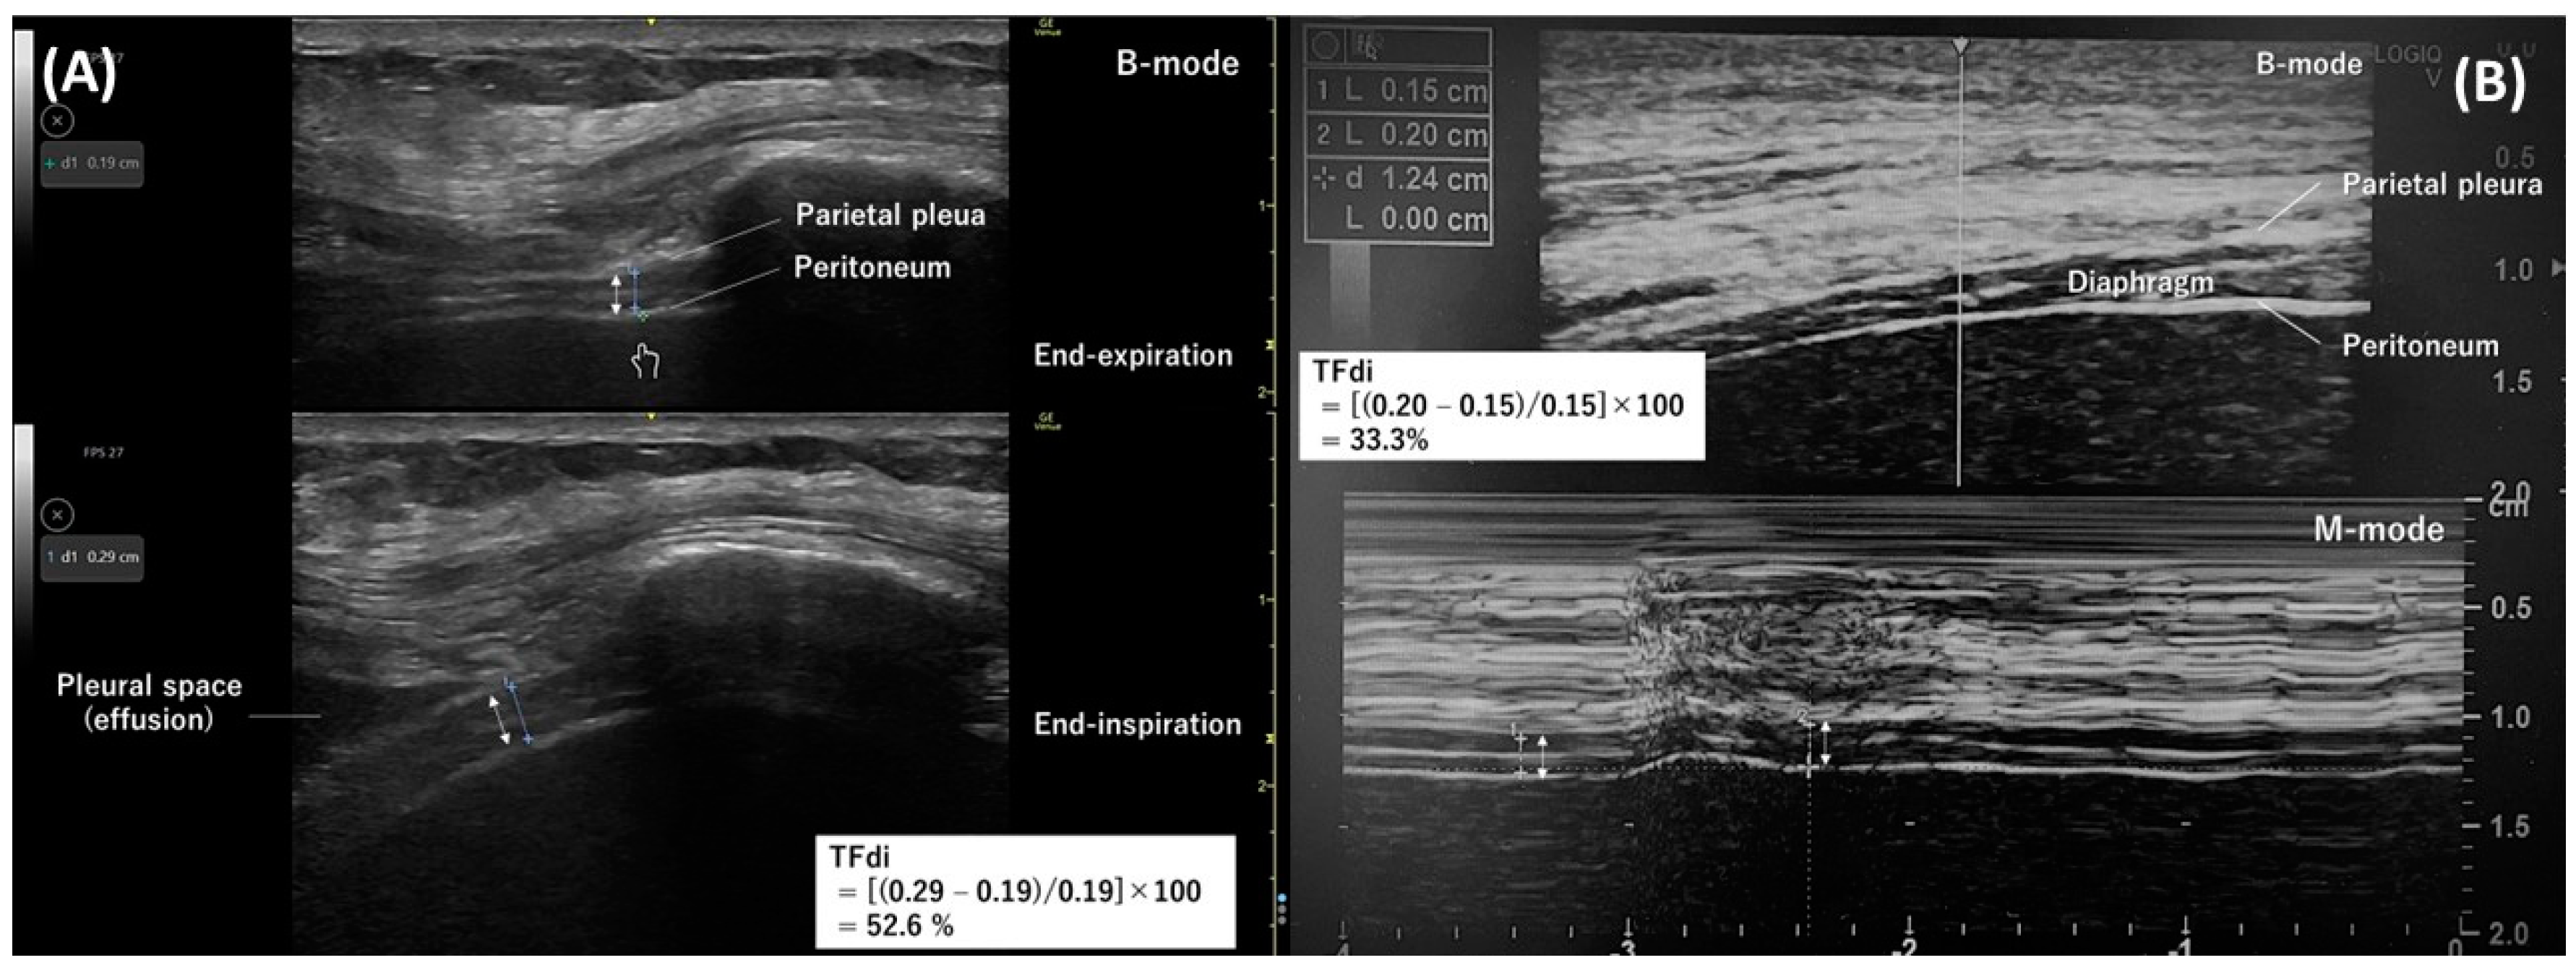

4.1. Evaluation of Diaphragm Thickness

4.2. Evaluation of Diaphragm Function

4.3. Evaluation of Respiratory Effort

- Goligher, E.C.; Laghi, F.; Detsky, M.E.; Farias, P.; Murray, A.; Brace, D.; Brochard, L.J.; Bolz, S.S.; Rubenfeld, G.D.; Kavanagh, B.P.; et al. Measuring diaphragm thickness with ultrasound in mechanically ventilated patients: Feasibility, reproducibility and validity. Intensive Care Med. 2015, 41, 642–649. [Google Scholar] [CrossRef]

- Cohn, D.; Benditt, J.O.; Eveloff, S.; McCool, F.D. Diaphragm thickening during inspiration. J. Appl. Physiol. 1997, 83, 291–296. [Google Scholar] [CrossRef] [PubMed]

- Vivier, E.; Dessap, A.M.; Dimassi, S.; Vargas, F.; Lyazidi, A.; Thille, A.W.; Brochard, L. Diaphragm ultrasonography to estimate the work of breathing during non-invasive ventilation. Intensive Care Med. 2012, 38, 796–803. [Google Scholar] [CrossRef]

- Umbrello, M.; Formenti, P.; Longhi, D.; Galimberti, A.; Piva, I.; Pezzi, A.; Mistraletti, G.; Marini, J.J.; Iapichino, G. Diaphragm ultrasound as indicator of respiratory effort in critically ill patients undergoing assisted mechanical ventilation: A pilot clinical study. Crit. Care 2015, 19, 161. [Google Scholar] [CrossRef]